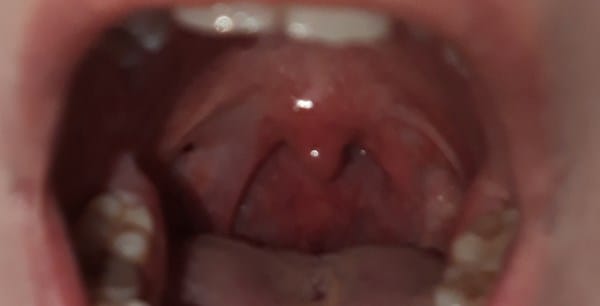

Hace algún tiempo me vi algo como una herida en el arco palatofaringeo, era roja y ahora es oscura, es pequeña y redonda, dudo de si en este momento esta más grande, me lo parece pero no puedo asegurarlo. A la vez tengo blanco en el arco palatofaringeo, en un lado más que otro, en el que más tengo me parece que se ha desplazado hacia atrás, ¿es eso posible? No lo sé. También tengo una herida en la parte de las encías que no se cura, es muy pequeña, me la vi como hace 3 semanas (No consigo que se vea bien en una fotografía para ponerla.) El síntoma que tengo relacionado con la boca/garganta es que me molesta al tragar, a veces me ha ocurrido y lo he relacionado con que había fumado de más, duraba un día o dos pero ahora se ha vuelto continuo. No tengo amígdalas así que no esta relacionado con algo de ellas. Soy fumadora de 2 paquetes diarios desde hace 10 años. ¿Todo esto estar relacionado simplemente con fumar o pueden ser síntomas de otra cosa? Empieza ha preocuparme.